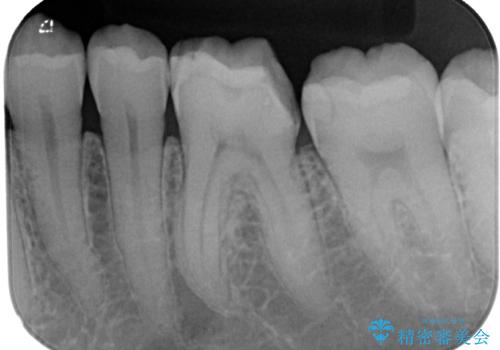

- 左下の詰め物が割れたとのことで来院された患者様です。現在に至るまで二度セラミックの詰め物(セラミックインレー)が割れているので強度面を考慮しセラミックの被せもの(セラミッククラウン)にて治療を行っていくことにしました。

拡大鏡視野下でセラミックインレー、虫歯の除去を行い、オールセラミッククラウンに適した形に整えました。